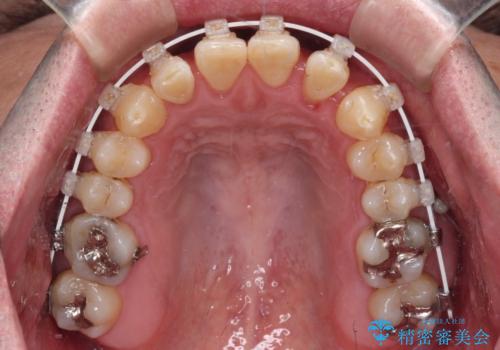

受け口を治す ワイヤー装置での矯正治療

- 上下前歯の反対咬合と左下奥歯の痛みを気にして来院された患者様です。

歯並びや口元の印象、奥歯の咬み合わせから、非抜歯にて矯正治療を行うこととしました。

矯正治療は、ワイヤー装置とマウスピース矯正との選択肢がありましたが、マウスピース矯正は自己管理が煩わしいことを気にされて、目立たないワイヤー装置にて行うこととしました。